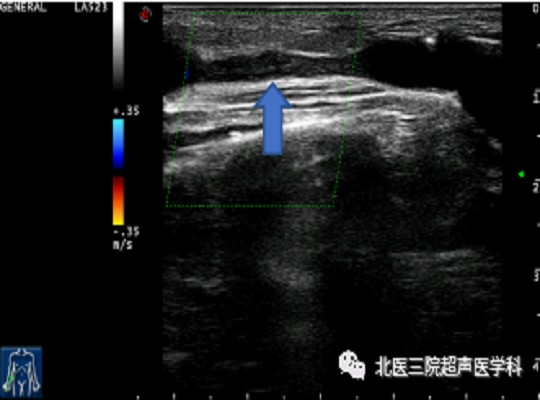

52岁男患,左前臂造瘘术后8年,触诊瘘口震颤减弱。超声证实头静脉近瘘口处严重狭窄